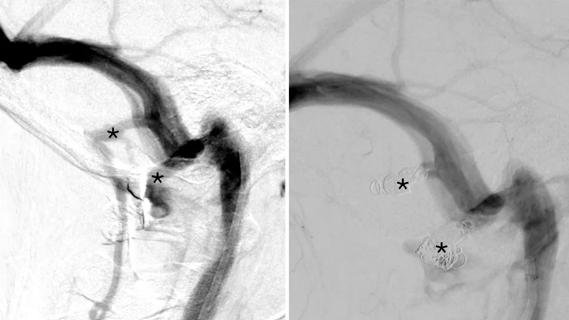

A rare immune-mediated disease

Susac syndrome is an uncommon immune-mediated disease affecting the eyes, ears and brain in a triad of vision loss, hearing loss and encephalopathy. It’s unclear why these organs are targeted in this condition. In the eye, branch retinal artery occlusions (BRAO) cause ischemia to parts of the retina leading to patches of vision loss. In the ear, the most distal parts of the blood supply of the cochlea are affected. As a result, the patient experiences low frequency hearing loss, which can be more profound as the disease progresses. When the corpus callosum is involved the symptoms can be broad, ranging from headaches and mood changes to severe encephalopathy.

Diagnosis is often made following MRI of the brain; the ischemic lesions in the corpus callosum are referred to as “snowball lesions.”

Alterations of the blood vessels appear to be a focus of the disease pathology, causing decreased blood flow and ischemia to the affected organs. Usually when we’re talking about blood vessel pathology in rheumatology, we’re referring to a vasculitis, but in Susac syndrome the pathology is non-inflammatory, categorized as a vasculopathy and, more specifically, an endotheliopathy. An endotheliopathy occurs when the endothelial cells lining the blood vessel swell, occluding the lumen of the vessel as well as disrupting the normal cell-to-cell barrier of the vessel. The cause of the endothelial swelling is unknown. The histology of the small affected blood vessel of Susac syndrome demonstrates the endothelial swelling, but not an influx of immune cells that is typically seen in a vasculitis.